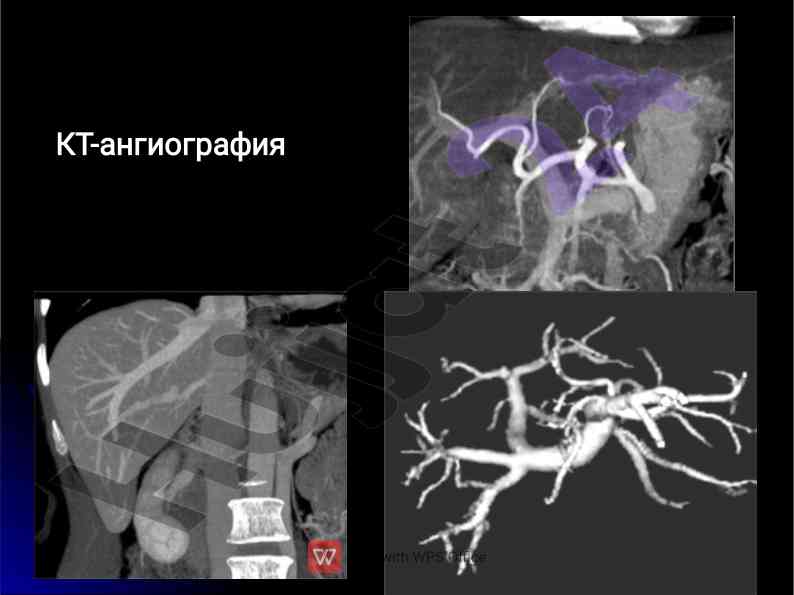

Jigar kasalliklari nur tashxisi va tashxis metodlari

Jigar kasalliklari uchun nur tashxisi va zamonaviy usullarni, shu jumladan kompyuter tomografiya va doppler tadqiqotlari haqida ma'lumot.